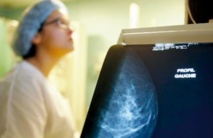

Les avantages des mammographies sont surestimés tandis que les risques sont sous-estimés, affirme un rapport publié mardi aux Etats-Unis qui apporte un nouvel éclairage sur le dépistage du cancer du sein.

Le principal danger de cette technique est le sur-diagnostic qui affecterait 19% des femmes, explique le Dr Nancy Keating, professeur adjointe de médecine à l'Hôpital Brigham and Women's et co-auteur de cette analyse publiée dans le Journal of The American Medical Association (JAMA). "Je dis à mes patientes que la mammographie n'est pas un test parfait", explique-t-elle.